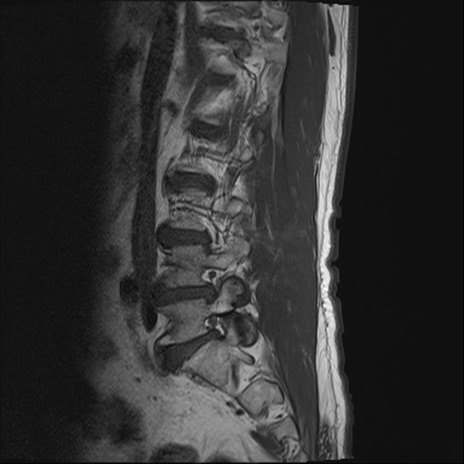

【整形】TIPS症例2 腰椎MRI T1WI(矢状断像)

【症例】70歳代男性

【主訴】左下肢痛

【現病歴】2週間前くらいから腰痛、左下肢痛あり。左臀部から大腿、下腿外側のしびれが常時ある。歩行とともに同部位の痛みあり。

【身体所見】Lasegue70-/60+、Bragard-/±、PTR ±/±、ATR -/-、IP 5/5、TA 5/4、TS 5/5、EHL 右第1足趾なし/3、FHL 5/5、hypersthesia(-)、足背動脈触知良好

異常所見と診断は?